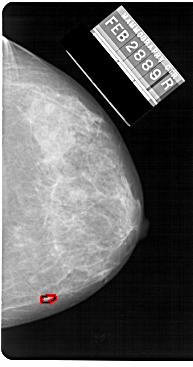

| ics_version 1.0 filename A-1219-1 DATE_OF_STUDY 28 2 1989 PATIENT_AGE 39 FILM FILM_TYPE REGULAR DENSITY 4 DATE_DIGITIZED 8 7 1998 DIGITIZER HOWTEK 43.5 SEQUENCE LEFT_CC LINES 5491 PIXELS_PER_LINE 3016 BITS_PER_PIXEL 12 RESOLUTION 43.5 NON_OVERLAY LEFT_MLO LINES 5491 PIXELS_PER_LINE 3271 BITS_PER_PIXEL 12 RESOLUTION 43.5 NON_OVERLAY RIGHT_CC LINES 5491 PIXELS_PER_LINE 2881 BITS_PER_PIXEL 12 RESOLUTION 43.5 OVERLAY RIGHT_MLO LINES 5491 PIXELS_PER_LINE 2836 BITS_PER_PIXEL 12 RESOLUTION 43.5 OVERLAY |

| FILE: A_1219_1.RIGHT_MLO.OVERLAY TOTAL_ABNORMALITIES 1 ABNORMALITY 1 LESION_TYPE CALCIFICATION TYPE PLEOMORPHIC DISTRIBUTION CLUSTERED ASSESSMENT 4 SUBTLETY 2 PATHOLOGY MALIGNANT TOTAL_OUTLINES 1 BOUNDARY |